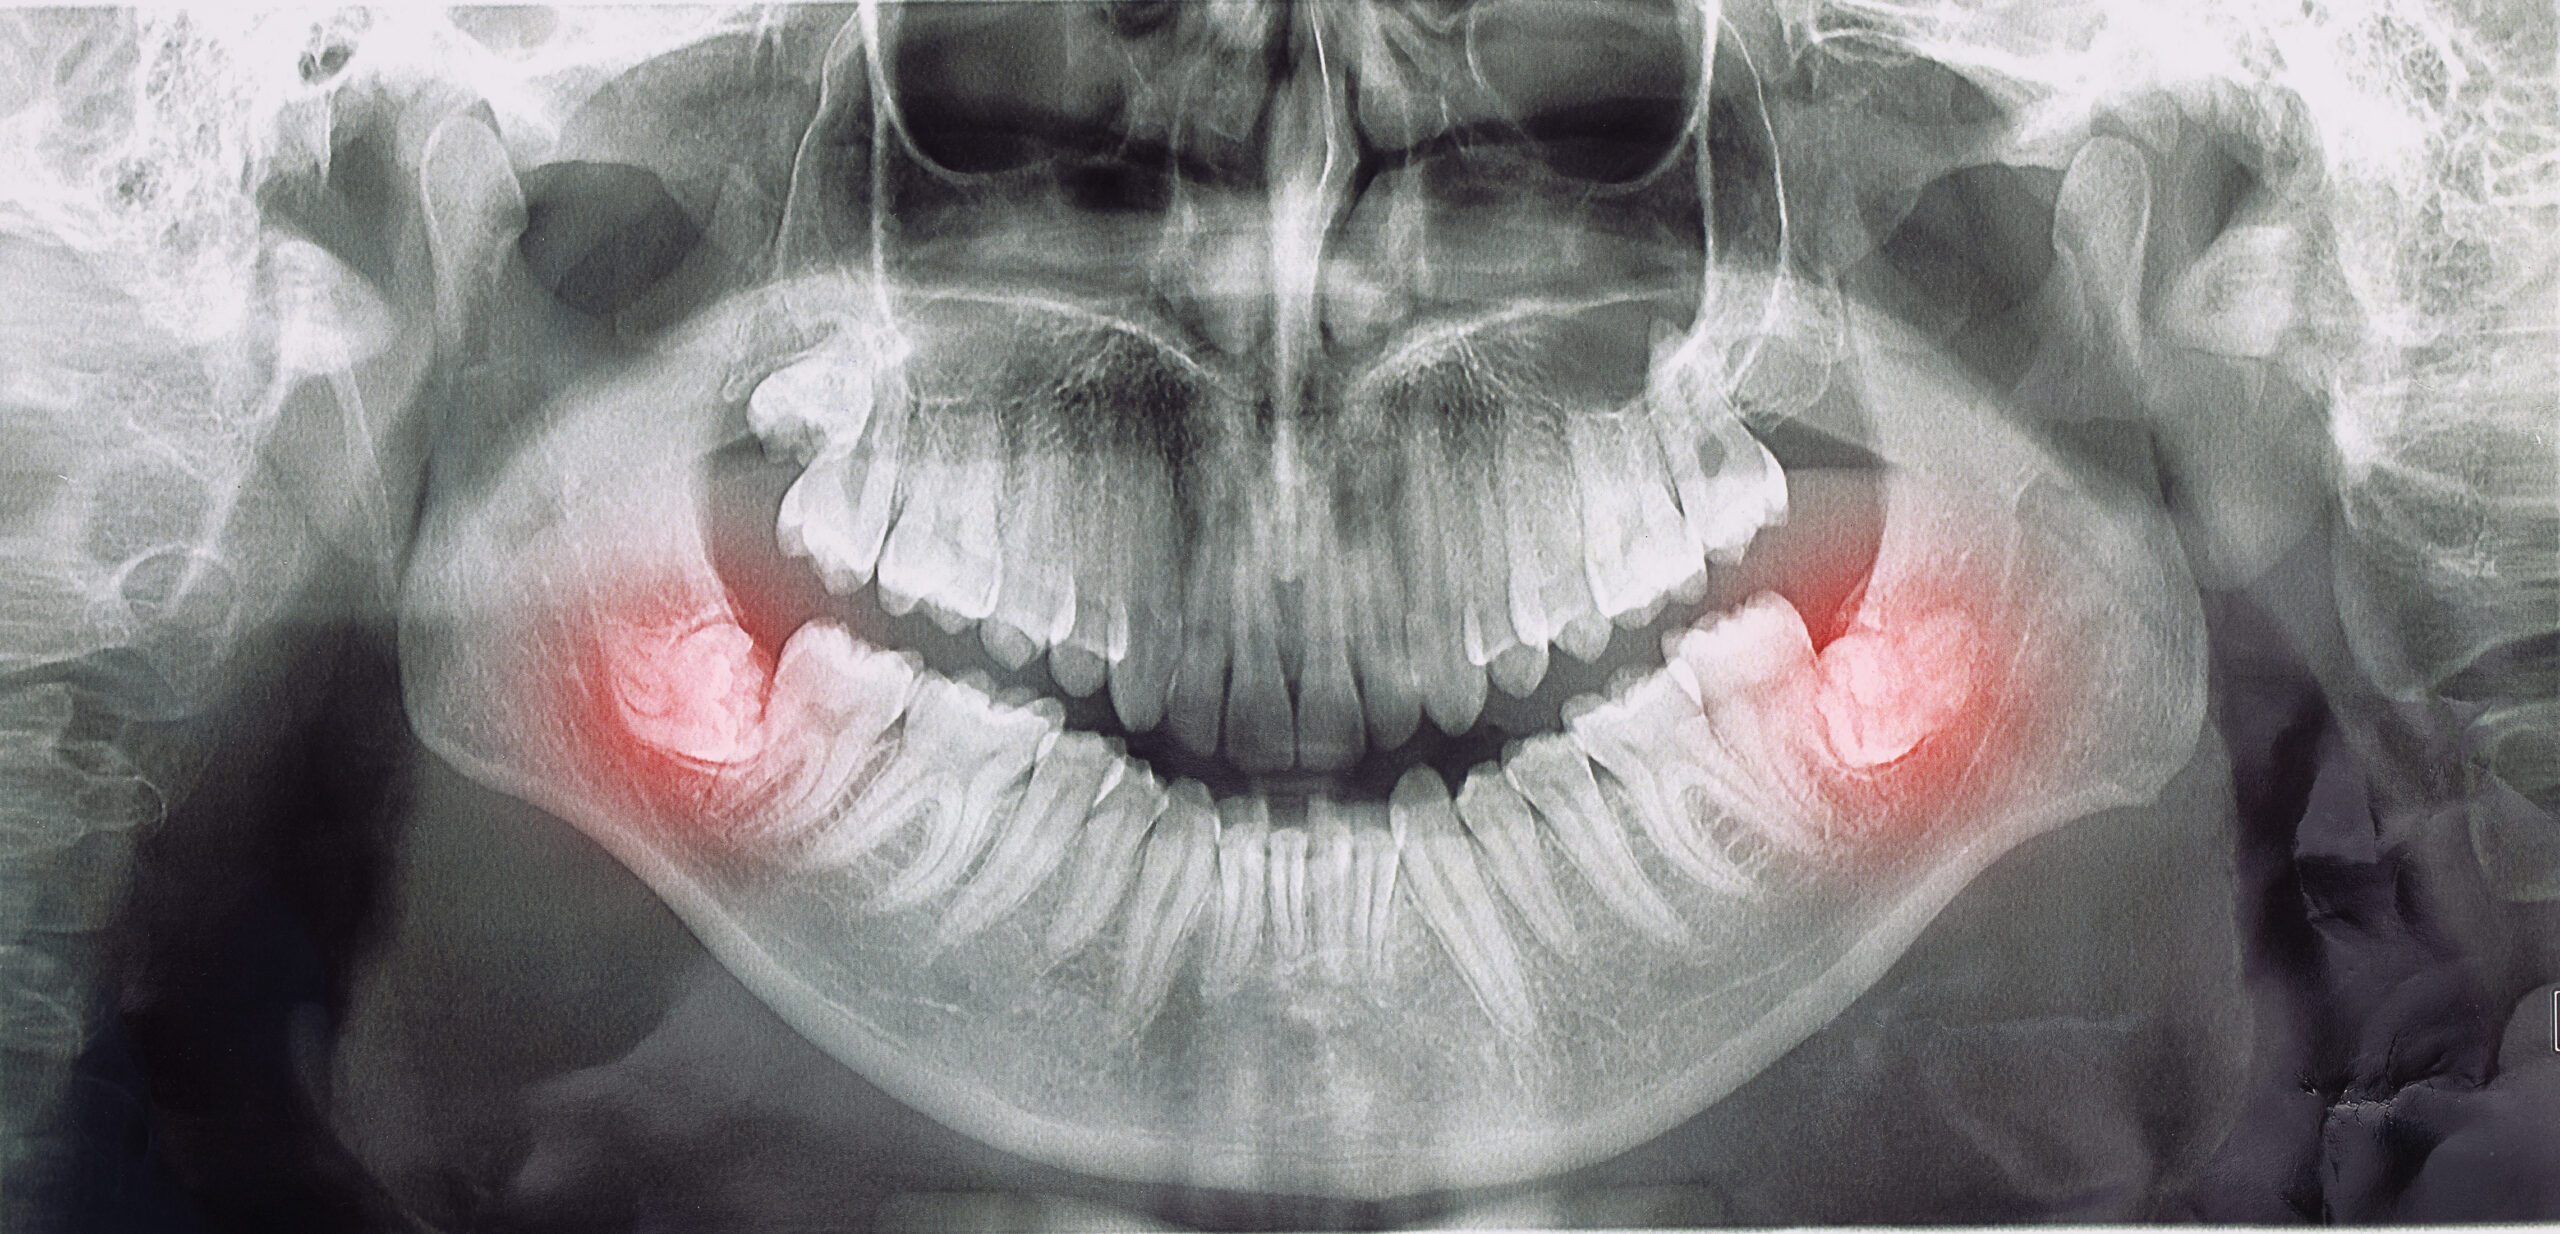

Ancak bazı durumlarda yirmi yaş dişi çene kemiği içinde yan yatık, eğimli veya gömülü pozisyonda kalabilir. Diş arkında yer darlığı olduğunda diş, diş eti ve kemik engeline takılır ve tam olarak süremez. Bu durumda diş tam gömülü veya yarı gömülü kalabilir ve ileride sorun oluşturma ihtimali nedeniyle çekimi gündeme gelebilir.

Gömülü dişler bazı vakalarda kist oluşumuna yol açabilir. Bu kistler kemik kaybına, çene genişlemesine, dişlerin yer değiştirmesine ve nadiren tümöral dönüşüme neden olabilir. Bu durumda diş çekilir ve kist dokusu temizlenir.